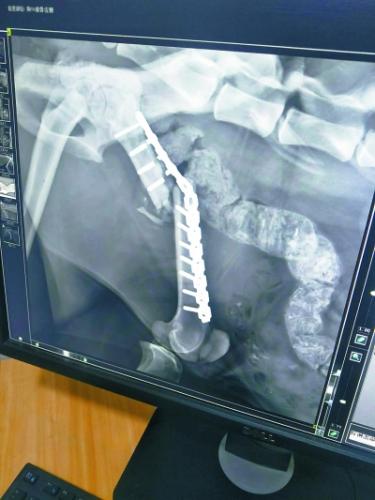

今年1月23日,饲养员发现“凌雪”步态异常,似乎又不能用力了。饲养员随即联系兽医,将“凌雪”麻醉后再次拉到动物医院拍片,结果令所有人大吃一惊,同时也心底一凉:“凌雪”左后肢股骨的加固钢钉折断了3根,钢板扭曲,股骨再次移位,它的腿又断了!

第一次手术植入的钢钉折断了3根

考虑到“凌雪”年事已高,已经打过11根钢钉,再次利用钢钉的话,可能会骨骼碎裂。而产生的碎骨还可能对肌肉等组织造成二次伤害,甚至感染致命。西宁野生动物园曾组织兽医和动物医院的医生进行了讨论,又向青海三甲医院的骨科专家进行了咨询,同时还向国内资深的野生动物救护人员、动物园兽医求教,但大家的意见差别很大。

,,在收到了海内外数十位专家、学者的反馈后,西宁野生动物园最终选择由北京派仕佳德动物医院的姚海峰博士主刀,为“凌雪”进行二次手术。

说到选择姚博士的原因,齐园长说,姚博士建议在二次手术时,用质量更好的骨板+髓内钉固定的方案,获业界认可。而且,他在得知雪豹救护的事情后,主动提出手术费用全免,展现了其关爱野生动物的情怀,也为动物园减轻了巨大的经济压力。